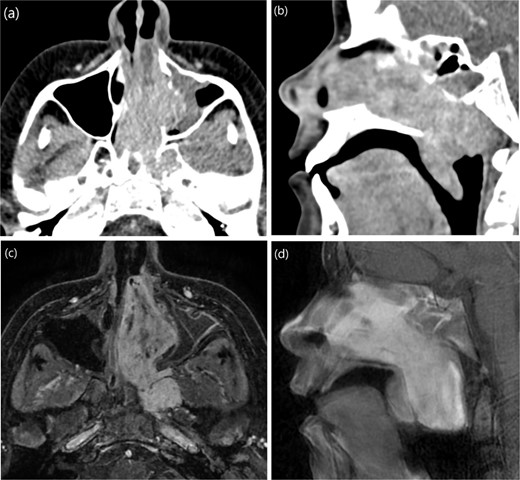

A 9-year-old previously healthy male was referred due to left nasal blockage and mild intermittent epistaxis persisting for 6 months. Nasal endoscopy revealed a clearly evident pinkish mass in the left nasal cavity. Non-contrast Computed Tomography (CT) of the paranasal sinuses (Fig. 1a and b) demonstrated a large, expansile, and ill-defined soft tissue mass with its epicenter in the left nasal cavity and nasopharynx. It extends to the left pterygopalatine fossa and the pterygomaxillary fissure, reaching the masticator space. The mass caused significant bone remodeling and expansion, with some erosions noted at the body and the left greater wing of the sphenoid bone, as well as the medial and lateral pterygoid plates. Additionally, the mass was seen extending to the lateral walls of the maxillary and ethmoid sinuses, bilateral sphenoid sinuses, and the inferior bony orbital wall. Contrast-enhanced Magnetic Resonance Imaging (MRI) showed a predominantly left-sided nasopharyngeal mass measuring 6.9 × 5.9 × 5 cm with increased vascularity (Fig. 1c). The mass replaced the left maxillary antrum, posterior ethmoid air cells, and sphenoid sinuses and invaded the left cavernous sinus (Fig. 1d). A pre-operative left ICA angiogram demonstrated the tumor’s blood supply originating from the vidian artery and inferolateral trunk, with the main supply arising from branches of the left internal maxillary artery (IMA). The vascular branches feeding the tumor from both IMAs were embolized.

(a) Axial non-contrast CT of the paranasal sinuses showing a soft tissue mass obliterating the posterior aspect of the nasal cavity, with extension and remodeling of the left pterygopalatine fossa into the infratemporal fossa. (b) Coronal image demonstrating superior extension into the left sphenoid sinus and left inferior orbital fissure. (c) Coronal T2-weighted MRI showing a large JNA with heterogeneous signal intensity and multiple flow voids consistent with hypervascularity. (d) Post-contrast coronal T1-weighted MRI demonstrating avid contrast enhancement and invasion of the left Meckel’s cave and cavernous sinus (arrow).